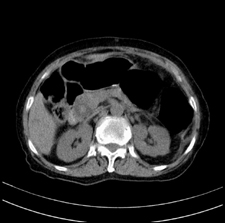

患者,女,75岁。腹痛,体黄5日,膝胸位时腹痛缓解。肝功能明日出来。彩超提示胆总管占位,未见血流信号。心电图提示s-t段改变。患者体质较弱,未能增强。

胆总管多发结石伴肝内外胆管轻度扩张。

胆总管上段,腔内有软组织密度影 ,ct值36-44hu。大家看有没有胆管癌的可能。

典型胆总管多发结石;增强扫描前后ct值是否发生改变是鉴别结石与占位的依据。

肝囊右.肾上腺囊肿

支持 胆总管结石,左侧胸膜增厚,心包膜增厚。